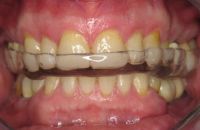

Voor de behandeling

Gebitsslijtage door een eetstoornis op jeugdige leeftijd. Door het vele spugen is er heel vaak maagzuur langs de tanden en kiezen gekomen waardoor bijna de gehele binnenzijde van de tanden is opgelost. Doordat de tanden zo dun zijn geworden, breken er gemakkelijk stukjes vanaf.